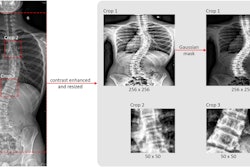

Full-body biplanar slot scanning is a type of low-dose digital x-ray imaging used to monitor scoliosis. Most patients are imaged in six-month intervals for a period of one to five years. This allows clinicians to estimate growth over time and compare them with statistical averages in the Anderson-Green method, the authors explained.

In this study, the authors aimed to leverage AI to improve these methods by training a convolutional neural network (CNN) model to automatically measure femorotibial length on x-ray images from a racially diverse set of pediatric patients.

The study data included 1,874 examinations from 523 pediatric patients aged 0 to 21 who underwent at least two slot-scanning radiographs in routine clinical care. Forty percent of the patients self-identified as white and not Hispanic or Latino and 60% self-identified as belonging to a different racial or ethnic group, the authors noted.